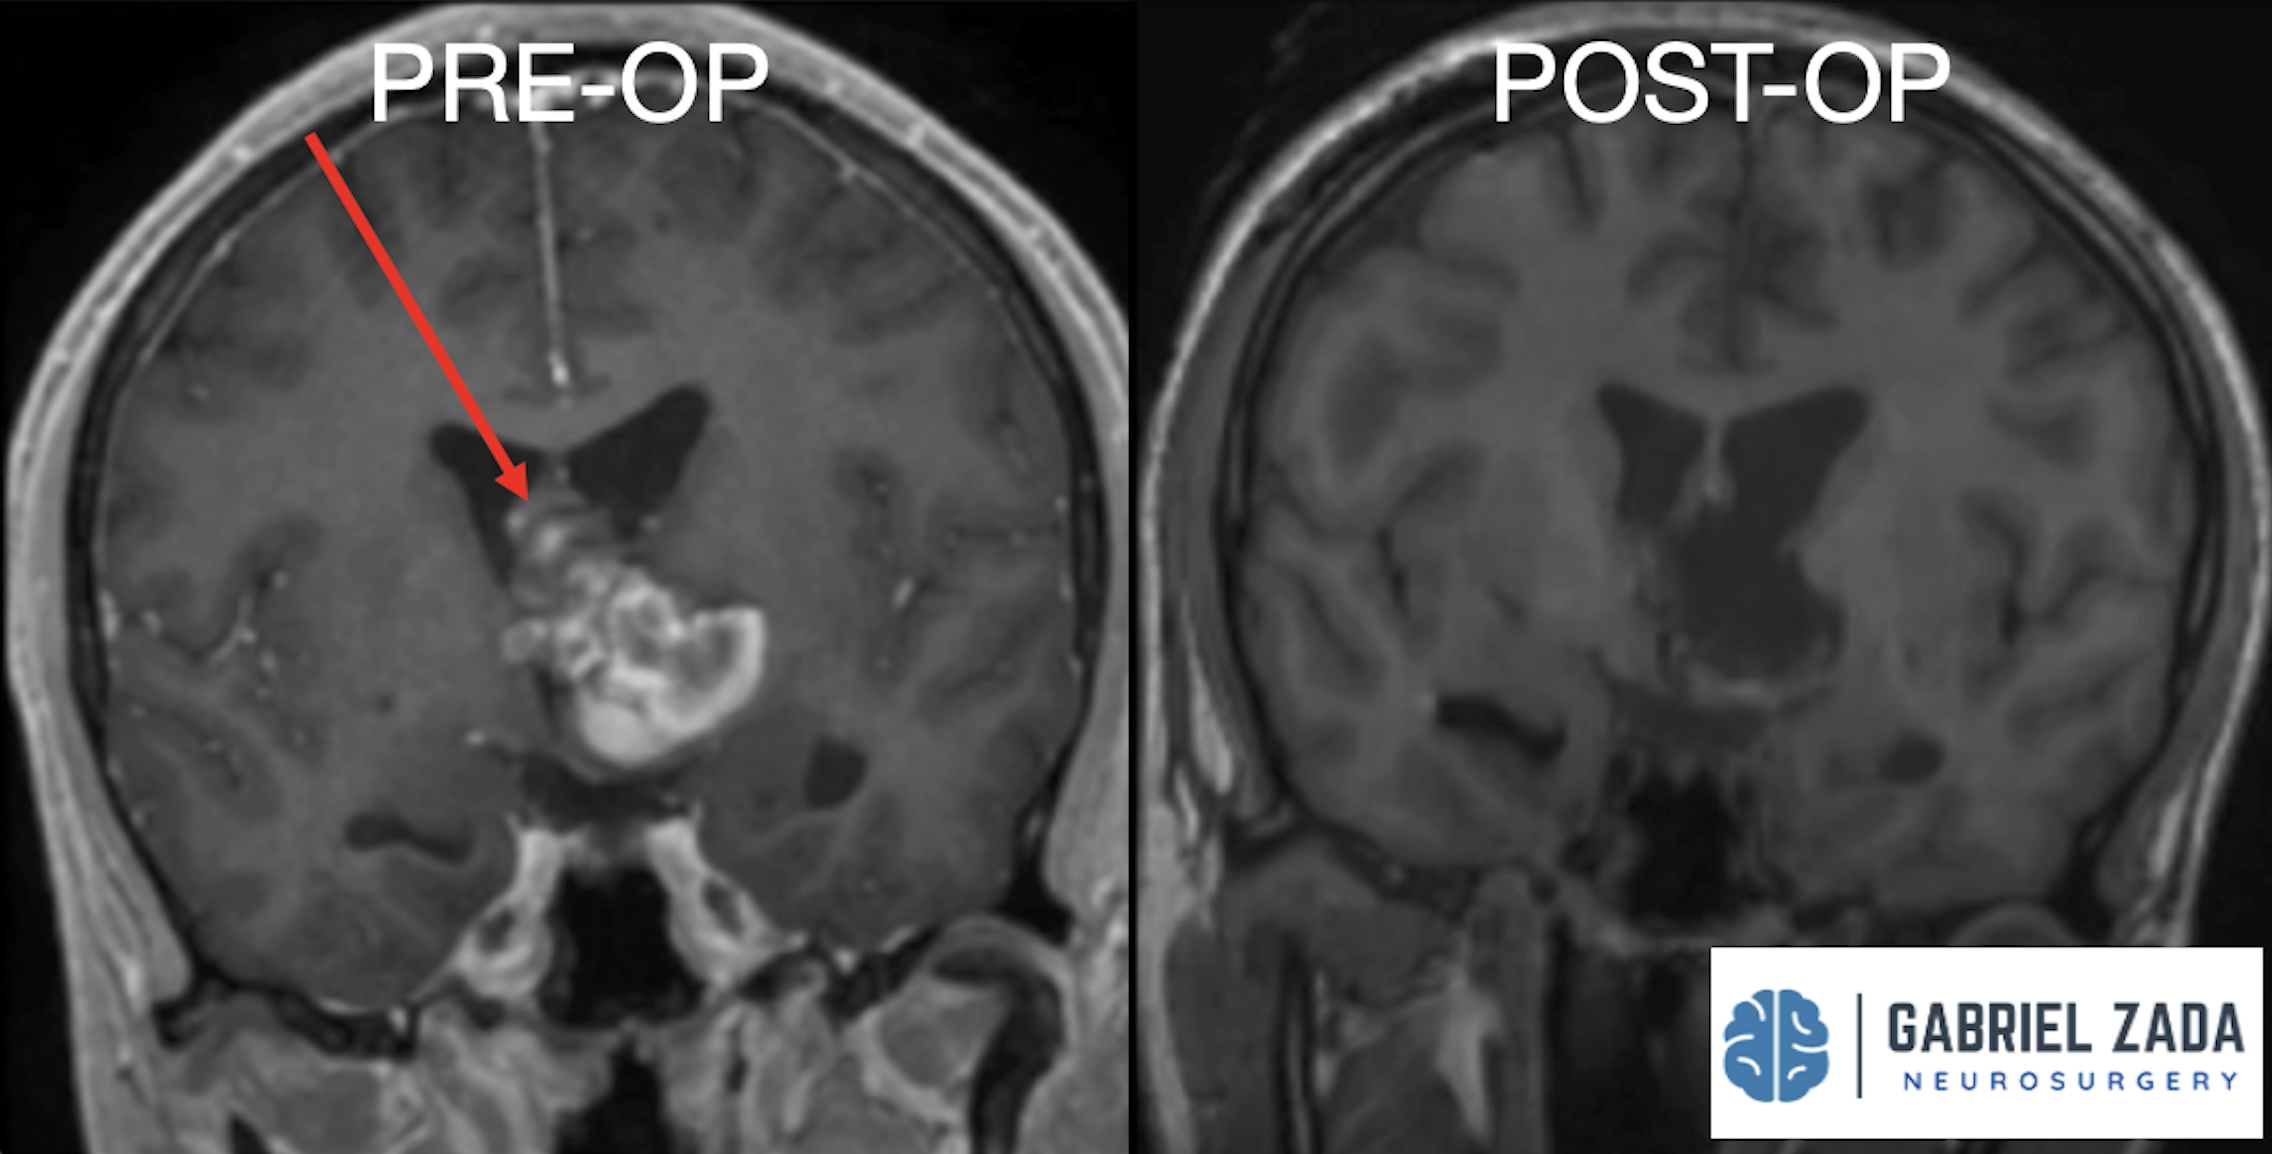

Explore this comprehensive gallery featuring pre‑ and post‑operative imaging of patients with skull‑base tumors treated by Gabriel Zada, MD, MS, FAANS, FACS. These cases highlight Dr. Zada’s expertise in advanced neurosurgical techniques and outcomes.

*Representative cases shown for educational purposes. All images de-identified. Individual results vary.